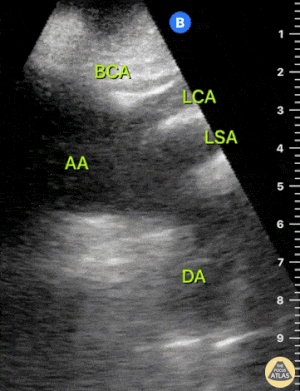

Ekokardiyografi (EKO): Normal Aort Örnekleri

Normal Aort Arkı – Suprasternal Görünüm

Normal Çölyak Trunkus ve SMA – Longitudinal

Normal Aort ve İliak Arterler – Transvers

Normal aort çapı 3 cm’den küçüktür. Herhangi bir seviyede çapın 5 cm’den büyük olması, uygun klinik bağlamda akut rüptür olasılığını akla getirmelidir.

Aort en az 4 seviyede görüntülenmelidir ve özellikle infrarenal segment dikkatle değerlendirilmelidir; çünkü AAA en sık bu bölgede görülür. İdeal olarak aortun tamamı kesintisiz şekilde taranmalıdır; ancak bu her zaman mümkün olmayabilir.

Ölçüm:

Transvers planda yapılmalıdır

En iyi konveks (curvilinear) prob ile değerlendirilir

Ölçüm dış duvardan dış duvara (outer wall to outer wall) yapılmalıdır